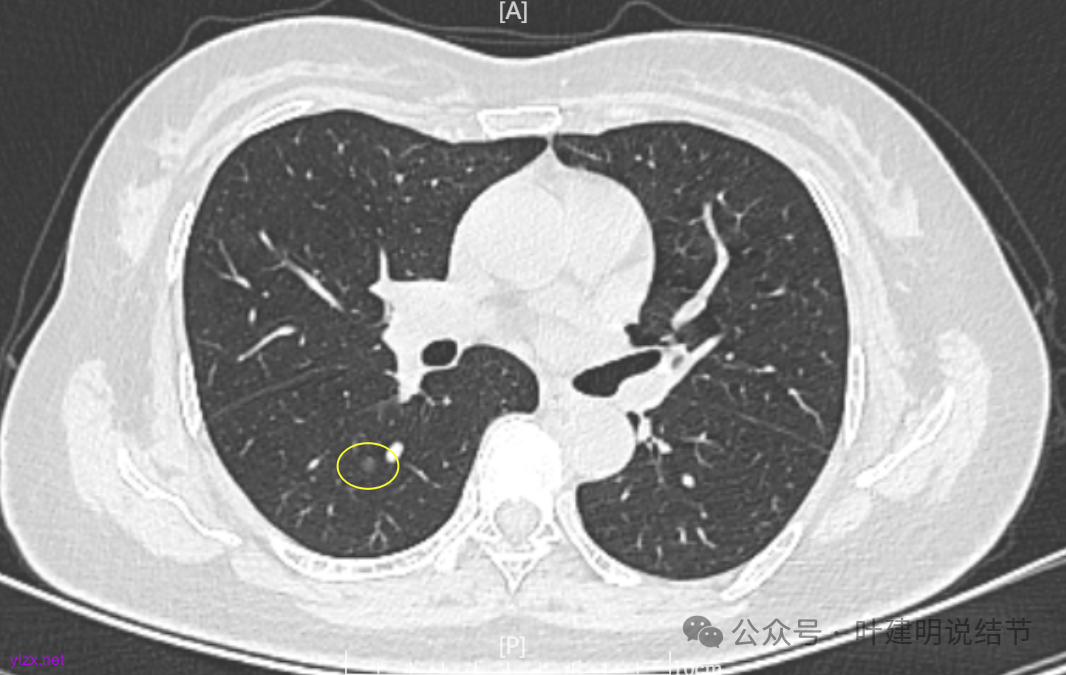

病灶7:右下叶胸膜下淡而微小的磨玻璃结节,考虑肺泡上皮增生可能性大。

我们发现其实各病灶与三年前比说不上显著进展。

两肺多发磨玻璃结节,主病灶混合密度且有小血管进入,表面不平有毛刺,考虑微浸润性腺癌或浸润性腺癌可能性大,其余部分考虑原位癌或微浸润性腺癌,部分考虑肺泡上皮增生或不典型增生可能。总体上对比2022年说不上太明显的进展。但对于是否手术来讲,我仍倾向当年的意见,左侧的可以考虑近期亚肺叶(个人倾向楔切)切除,右侧的先随访,以后有进展并风险增加再考虑干预处理。因为要拉长两次手术的间隔,这样对机体的创伤与恢复更加有利一些。若定要仍不开刀,则建议要4-6个月复查,不过个人不太主张过于保守随访,对于像主病灶这种有少许实性成分的,不能保证肯定安全。意见供参考!